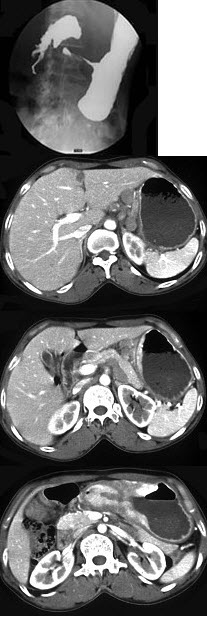

女,56岁,上腹部钝痛、腹胀不适1月余,纳差、消瘦,影像检查如图,最可能的诊断是( )

A:胃幽门管溃疡

B:胃腺癌并幽门狭窄

C:胃淋巴瘤

D:胃间质瘤

E:胃恶性间质瘤